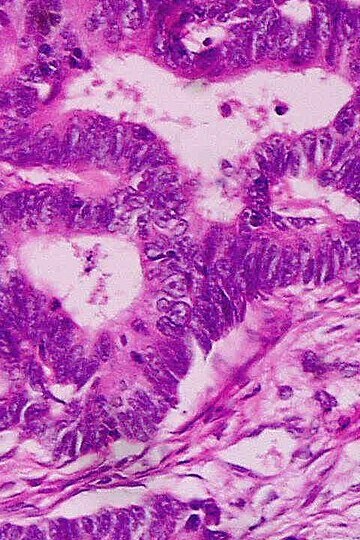

El éxito de las inmunoterapias contra el cáncer se basa en la selección de neoepítopos (antígenos asociados a tumores) altamente expresados. Estas terapias favorecen preferentemente a las neoplasias malignas con una elevada carga mutacional. Aquí demostramos que las respuestas tempranas de los interferones de tipo I median el éxito de los inhibidores de puntos de control inmunitario, así como la propagación de epítopos en tumores poco inmunogénicos, y que estas respuestas de interferones pueden potenciarse mediante la administración sistémica de partículas lipídicas cargadas con ARNm que codifica antígenos no específicos del tumor.

En ratones, las respuestas inmunitarias de los tumores sensibles a los inhibidores de puntos de control fueron transferibles a tumores resistentes y dieron lugar a una mayor inmunidad con propagación antigénica que protegió a los animales de una nueva exposición al tumor. Los hallazgos muestran que la resistencia de los tumores a la inmunoterapia viene dictada por la ausencia de una respuesta al daño, que puede restaurarse potenciando las respuestas tempranas de los interferones de tipo I para permitir la propagación de epítopos y respuestas autoamplificadoras en tumores refractarios al tratamiento.

Los inhibidores de puntos de control inmunitarios (PCI) han revolucionado el tratamiento del cáncer. Al bloquear las vías que regulan el sistema inmunitario, estos anticuerpos monoclonales pueden mejorar la inmunidad, potenciar la actividad de las células T y reiniciar el reconocimiento y la destrucción de las células cancerosas. El éxito de la terapia con PCI se basa en una respuesta de las células T activadas contra los neoepítopos cancerosos, lo que favorece preferentemente a las neoplasias malignas con una alta carga mutacional tumoral (CMT). Sin embargo, muchos tumores con alta CMT son resistentes a los PCI y los cánceres con baja CMT pueden tener un número limitado de pacientes que responden al tratamiento. La interacción que impulsa la inmunogenicidad del cáncer y la respuesta a la inmunoterapia sigue sin entenderse bien.

Muchos tumores logran desarrollar resistencia a los PCI al secuestrar las vías de señalización del IFN tipo I (IFN-I), frustrando así la inducción de la inmunidad terapéutica. La producción sostenida de IFN-I puede precipitar un estado inmunorregulador y un entorno inflamatorio crónico perjudicial para la inmunidad adaptativa y la respuesta a los PCI. Sin embargo, el IFN-I es vital para la respuesta inmunológica a través de la activación de los receptores de reconocimiento de patrones y desempeña un papel fundamental en la facilitación de las interacciones entre las células dendríticas y las células T efectoras. Basándose en estos efectos, se planteó la hipótesis de que el IFN-I temprano es fundamental para iniciar la inmunoterapia contra el cáncer y la propagación de epítopos en neoplasias malignas inmunogénicas, y podría inducirse artificialmente mediante biomiméticos codificadores de ARN en tumores poco inmunogénicos.

Descubrimos que el IFN-I temprano determinaba la magnitud de la respuesta a los PCI en tumores sólidos murinos tanto intracraneales como extracraneales y dictaba la inmunogenicidad del cáncer en tumores que respondían a los PCI de una manera que era transferible a neoplasias malignas previamente resistentes. Este conocimiento contribuyó al desarrollo de vacunas de ARN mensajero no específicas para tumores que restauraban la inmunidad dependiente del IFN-I en modelos paralelos para tumores resistentes a los PCI, lo que permitía la propagación de epítopos y mejoraba la supervivencia.

El estudio demostró que las respuestas tempranas de los interferones de tipo I median el éxito de los inhibidores de los puntos de control inmunitario, así como la propagación de epítopos en tumores poco inmunogénicos. Estas respuestas de los interferones pueden potenciarse mediante la administración sistémica de partículas lipídicas cargadas con ARN que codifica antígenos no específicos del tumor. En ratones, las respuestas inmunitarias de los tumores sensibles a los inhibidores de puntos de control fueron transferibles a tumores resistentes y mejoraron la inmunidad con la propagación antigénica que protegió a los animales de una nueva exposición al tumor. Estos resultados demostraron que la resistencia de los tumores a la inmunoterapia está controlada por la ausencia de una respuesta al daño, que puede restaurarse potenciando las respuestas tempranas del interferón tipo I para permitir la propagación de epítopos y las respuestas autoamplificadoras en tumores refractarios al tratamiento.